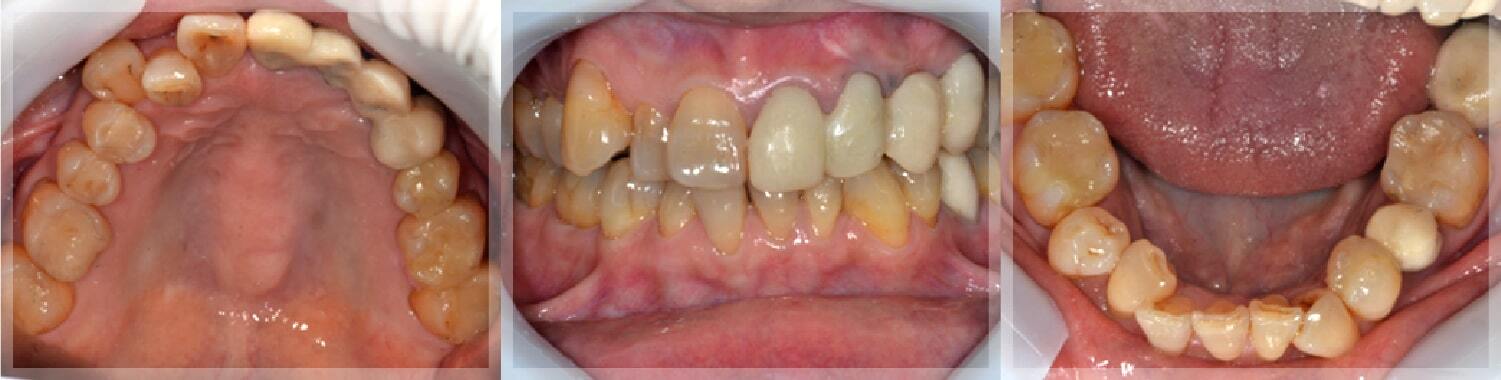

治療完了時

治療結果

マウスピースを使い出して2週間で主訴は改善し、その後噛み合わせも安定しています